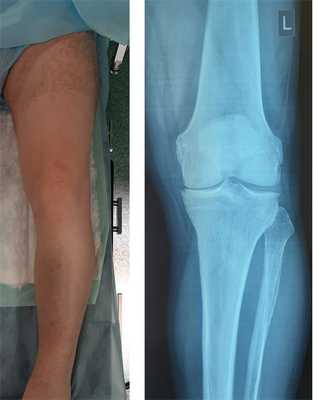

Клинический пример лечения медиального артроза коленного сустава при помощи высокой вальгизирующей корригирующей остеотомии большеберцовой кости.

Пациент Х 54 лет, активный мужчина, занимается лыжным спортом, длительное время (около 10 лет) начал отмечать болезненность во внутреннем отделе коленного сустава при нагрузке.

При осмотре обращает на себя внимание варусная деформация коленных суставлв, более выраженная слева.

![артроз коленного сустава, варусная деформация, боль в колене]()